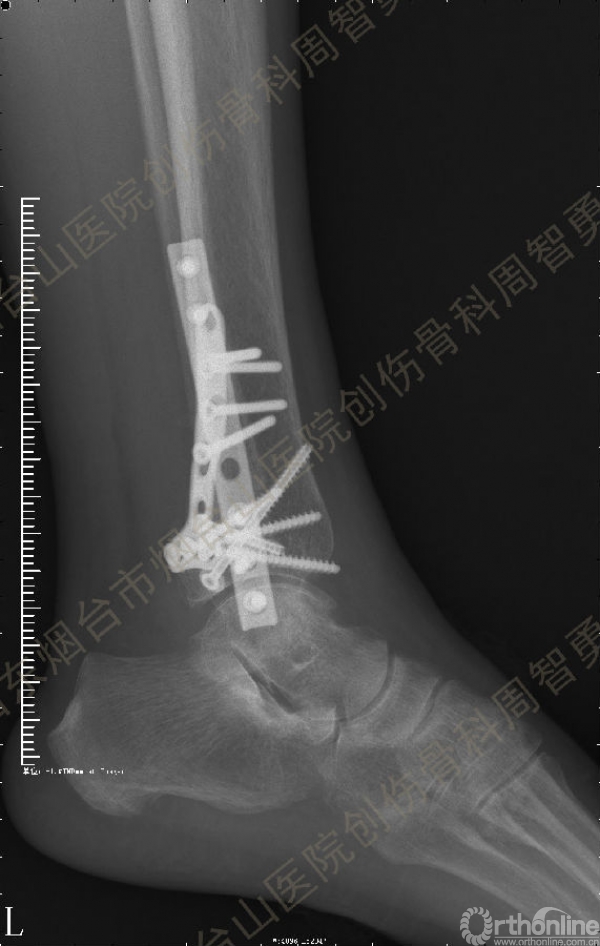

患者取俯卧位,轻度屈膝,小腿下垫枕使足离开床面。取长约10cm的踝关节后外侧切口,皮肤切口位于外踝后缘与跟腱的中线,远侧延伸至外踝尖。皮下与深筋膜间显露、保护小隐静脉和腓肠神经,纵向切开腓骨肌浅面深筋膜,显露腓骨肌腱。将腓骨肌腱牵向外侧显露后浅室和后深室间隔,透过肌间隔可见踇长屈肌。切开肌间隔显露踇长屈肌并向内侧牵开,显露胫骨远端后侧骨折块。保护腓动脉、下胫腓后韧带和骨折块上的骨膜。在后内侧骨折块和后外侧骨折块中间的骨折线切开骨膜并骨膜下游离数毫米,分别以胫后肌腱腱鞘和下胫腓后韧带为铰链,将后内侧骨折块和后外侧骨折块翻向内侧和外侧。显露后内侧骨折块腹侧向近端塌陷的骨软骨骨折块。见后内侧骨折块腹侧有约4.0 mm×3.0 mm×3.0 mm大小向近端塌陷的骨软骨骨折块,给予切除。取长约5cm的踝关节后内侧入路,切开皮肤皮下并适当向两侧游离,不切开屈肌支持带,仅切开后内侧骨折块内侧缘和近侧缘的骨膜。通过后外侧入路和后内侧入路显露后内侧骨折块的外侧缘、近侧缘和内侧缘,直视下解剖复位后,2.0 mm克氏针临时固定。直视下解剖复位后外侧骨折块,并用2.0 mm克氏针临时固定。返回后外侧切口,向外侧游离皮瓣,内牵腓骨长短肌腱显露外踝骨折,解剖复位后用2.0 mm克氏针临时固定。术中透视显示骨折块解剖复位。一枚4.0mm空心螺钉固定于后内侧骨折块的内上缘,另一枚4.0mm空心螺钉固定于后丘,5孔桡骨远端T型接骨板抗滑固定于后内侧骨折块和后外侧骨折块。8孔1/3管状板固定外踝骨折。术中Cotton试验阳性,复位下胫腓联合后,1枚3.5mm皮质骨螺钉固定。Chaput骨折块未作处理。术中及术后X线摄片示骨折解剖复位,内固定物位置正确。术后,踝关节于背伸0~5°,短腿石膏后托或支具固定2周。2周去除外固定开始踝关节主动功能练习。术后8周,X线片示骨折解剖复位,骨折线模糊,内固定物在位(图3a,b)。术后第11周开始部分负重,第13周拔除固定下胫腓联合的螺丝钉,逐步开始完全负重。术后4个月复查:X线片示骨折解剖复位,骨折线消失,内固定物在位;左侧踝关节主动背伸较健侧差10°,跖屈差10°;踝关节无疼痛,肌力较健侧无明显减退。

↑ 图 3b

图 3 术后8周X线片示骨折解剖复位,骨折线模糊,内固定物在位